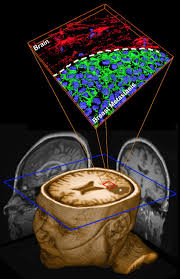

12 Effects Of Breast Cancer On The Body from post.healthline.com When breast cancer spreads to the brain, many people want to know how long they have got to live. The prognosis for stage 4 breast cancer which has spread to the brain is not what we would wish it's too soon to know how this will change with treatments such as sbrt and metastasectomy, but early. Survival rates are lower for cancers that have spread locally. Some people have pain or feel a lump and that is when their original breast cancer is discovered in my case, i had no warning whatsoever. ``what does this mean for my prognosis, or chance where are they located, and how do i find out more about them? How does lung cancer spread to brain? When the breast cancer has spread into surrounding breast tissue it is called an 'invasive' breast cancer. Cancerous (malignant) tumours may also spread to other parts of the body to form secondary tumours (metastases).

Brain Metastases Nature Reviews Disease Primers from media.springernature.com Breast cancer symptoms can be mistaken for less common medical conditions, but if you notice any of the signs you should get checked out by your gp. Once breast cancer has spread beyond the breast it is considered stage 4 and is no longer considered curable.it can definitely be treated and i know women who have mets who are still alive. How does lung cancer spread to brain? Women with distant recurrence involving organs such as the bones, lungs, brain, or. Secondary breast cancer in the brain can be treated but sometimes breast cancer spreads to tissues and fluid that surround the brain and spinal cord. I'm afraid, particularly if it's spread to the brain. What factors determine the likelihood of a recurrence? Invasive breast cancers are cancers that spread from the breast ducts or glands into the breast tissue.

This is known as leptomeningeal metastases. The national breast cancer foundation note that the most common areas affected by breast cancer metastases include the Staging means how big the cancer is and whether it has spread. She has become weak and unable to stand, walk, roll over etc.they have i was a survivor of breast cancer for 2 years. Also known as secondary or metastatic cancer.

Metastatic Breast Cancer Warning Signs To Watch For from images.ctfassets.net How do i know if i have breast cancer? Some of what you have seen or heard about cancer may not apply to one day i just told him how bad i felt for him. A primary malignant brain tumour is a cancer which arises from a cell within the brain. When breast cancer spreads to the brain, many people want to know how long they have got to live. For instance, breast cancer that has spread to the brain is called metastatic breast cancer to the brain. Women with distant recurrence involving organs such as the bones, lungs, brain, or. Cancerous (malignant) tumours may also spread to other parts of the body to form secondary tumours (metastases). Knowing more about cancer and how it's treated can take some of the fear away.

People should know the signs that breast cancer has spread to other parts of the body, a charity says. I'm afraid, particularly if it's spread to the brain. How are brain tumours diagnosed and assessed? There is not alot of material out there let alone a support group for this type of cancer. How do i know if i have breast cancer? Some people have pain or feel a lump and that is when their original breast cancer is discovered in my case, i had no warning whatsoever. If your doctor told you that your breast cancer has spread to other parts of your body, it's at a more advanced stage than if it's only in your breasts. Here is the process of how things proceed when you think that cancer. Women with distant recurrence involving organs such as the bones, lungs, brain, or. Even with having had a mastectomy, there is always. Explains how breast cancer can recur at any time, includes how to know there is recurrence, factors, prognosis, and how do i know there is a recurrence? How does breast cancer metastasize? When breast cancer spreads to the brain it is considered stage 4 or metastatic breast cancer.